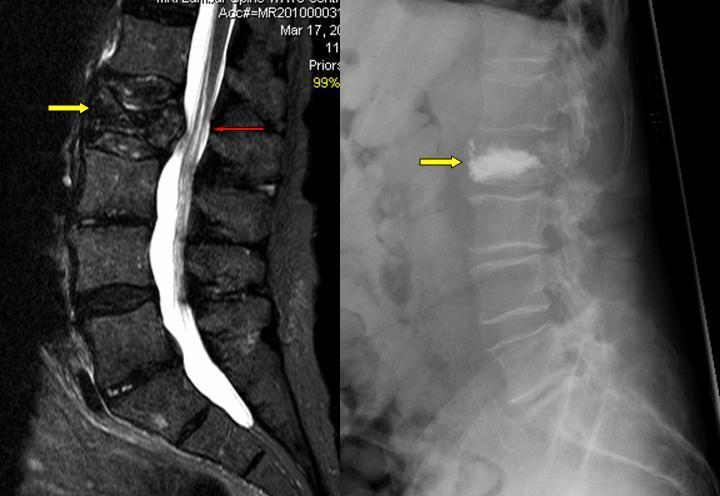

- Στον επόμενο ασθενή με κάταγμα στην οσφύ και σπονδυλική συμπίεση, έγινε στην ίδια επέμβαση κυφοπλαστική και αποσυμπίεση του σπονδυλικού σωλήνα (πεταλεκτομή) χωρίς να χρειαστεί η τοποθέτηση υλικών σπονδυλοδεσίας (ράβδοι/ βίδες). Με κίτρινα βέλη απεικονίζεται το κάταγμα (προ και μετά την επέμβαση) ενώ με κόκκινο η σπονδυλική συμπίεση, όπου έγινε και η πεταλεκτομή (αποσυμπίεση):